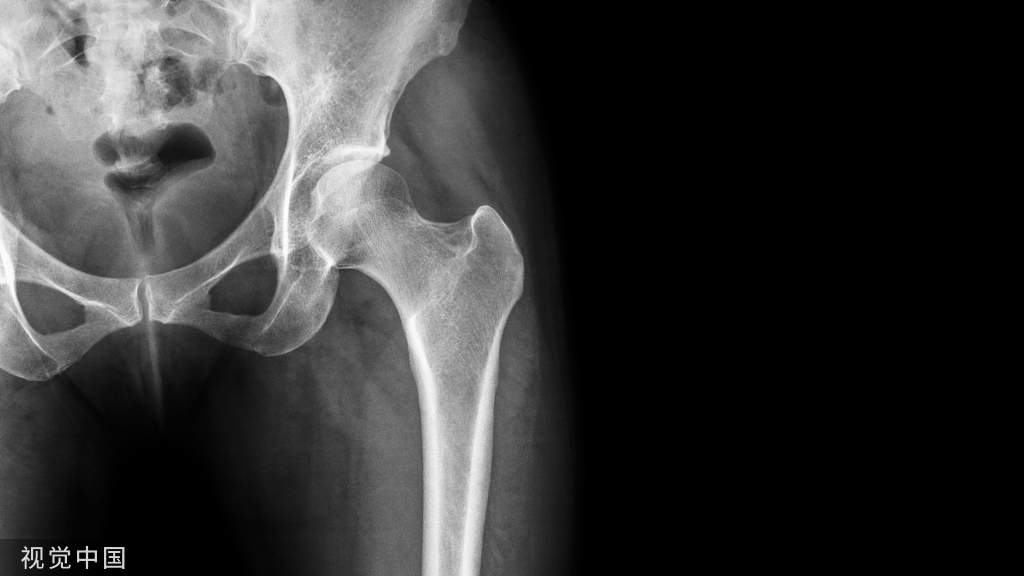

X光片看上去就有点严峻:双侧坏死的面积较大,所幸还没有塌陷。

如果根据以上影像进行判断的话,可以行髓芯减压或者植骨。但是,看了下面的CT,很多人恐怕就要重新考虑治疗方案了。